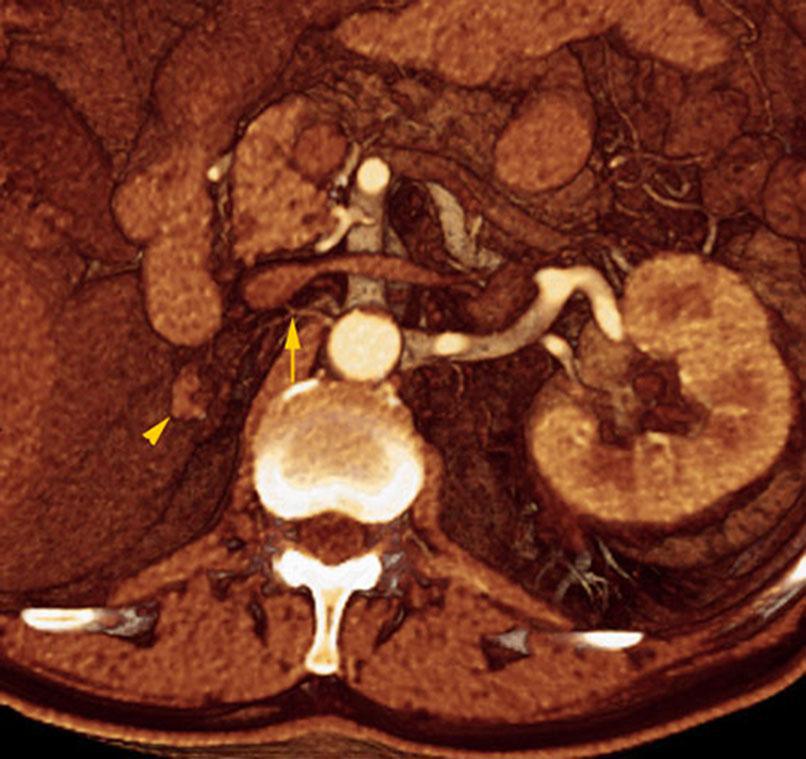

Riñón único pélvico